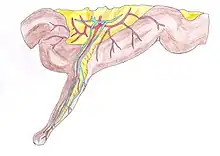

| Schematic drawing of a Meckel's diverticulum with a part of the small intestine. | |